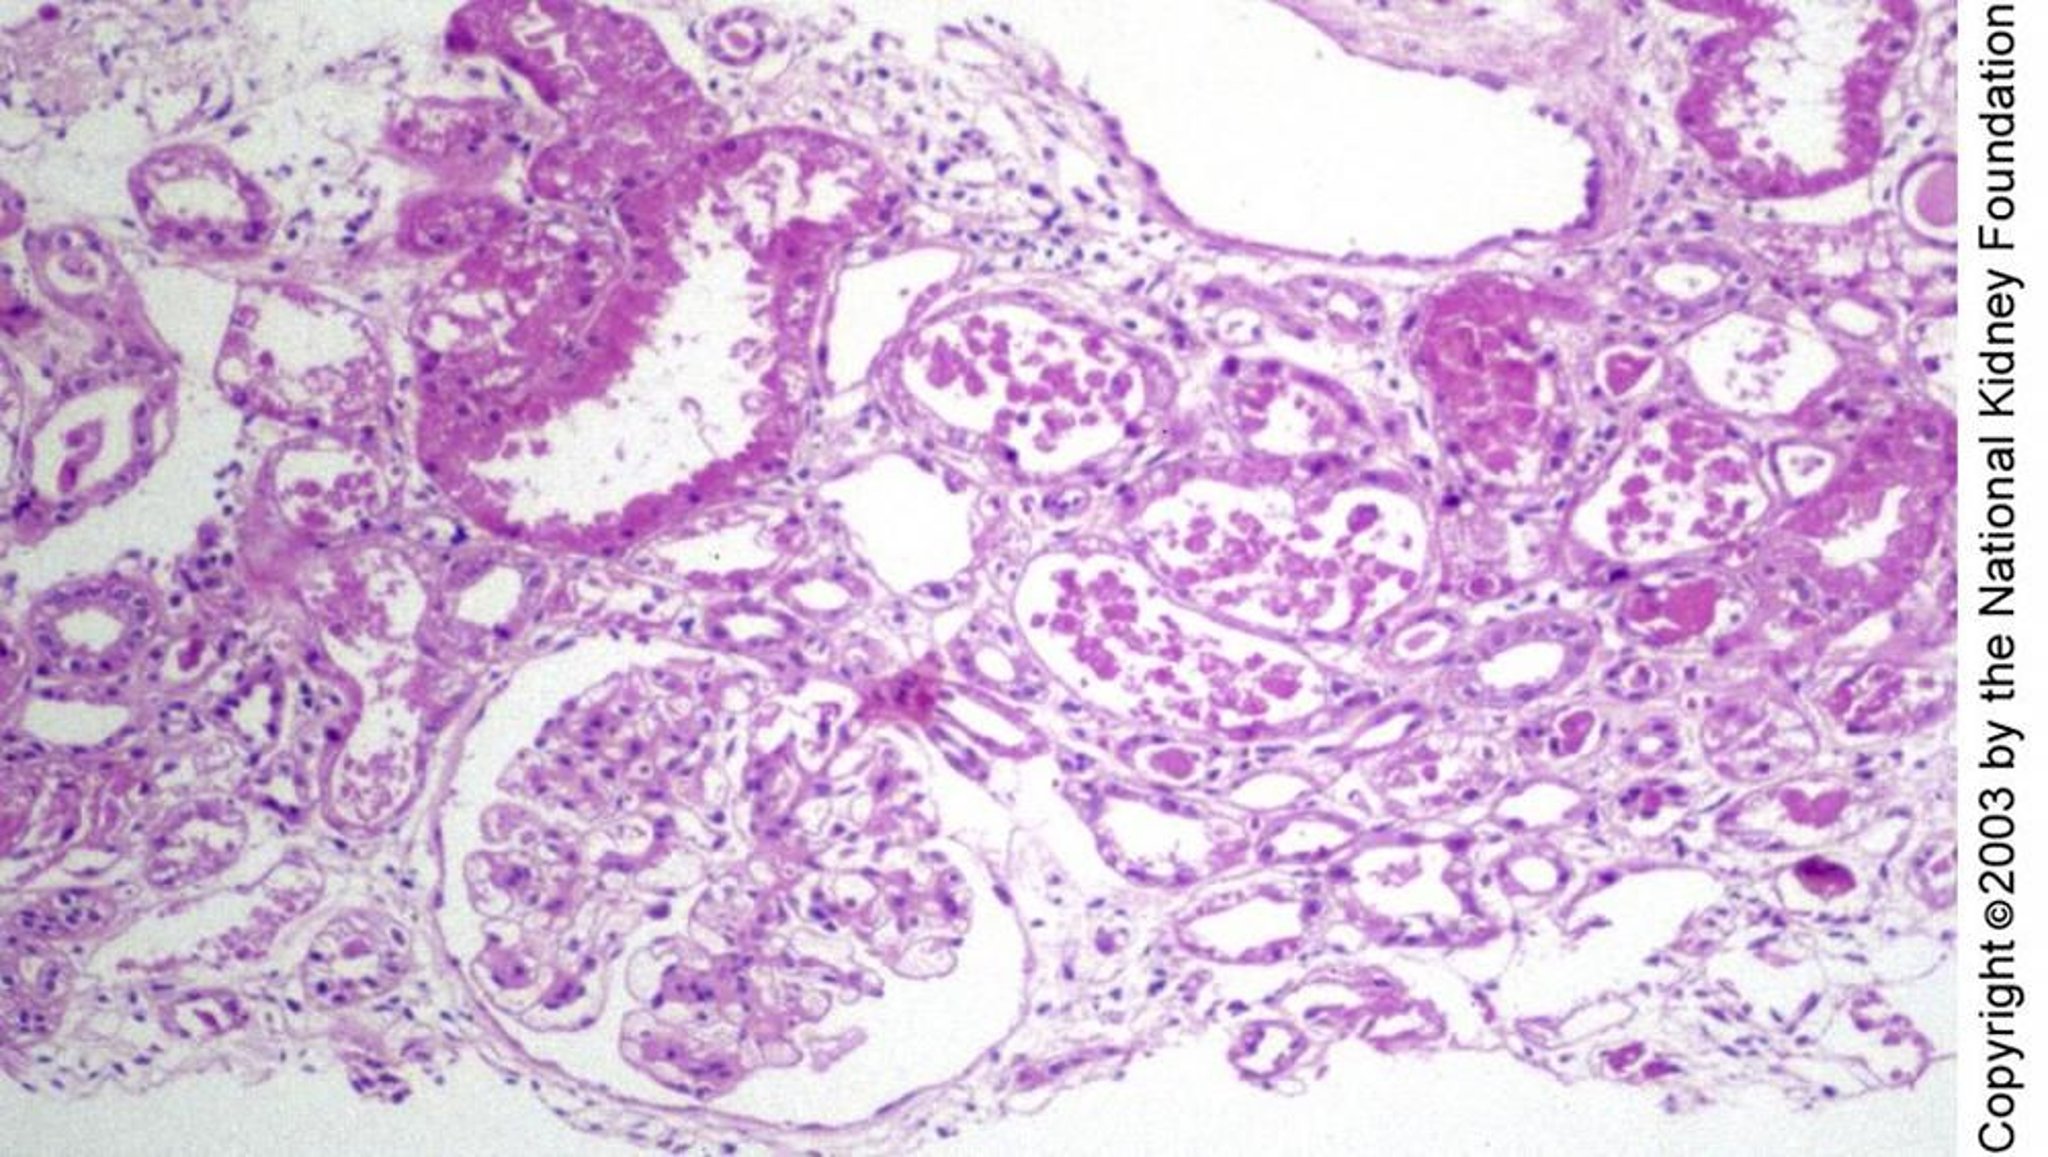

Necrosi tubulare acuta

La lesione tubulare nella necrosi tubulare acuta può manifestarsi istologicamente come rigenerazione dell'epitelio tubulare appiattito senza necrosi, come visto a destra del glomerulo, rigonfiamento e degenerazione cellulare individuale, come in alto a sinistra, o come necrosi franca, come nell'immagine nel mezzo (colorazione con acido periodico di Schiff, ×100).

Imagine fornita da Agnes Fogo, MD, and the American Journal of Kidney Diseases' Atlas of Renal Pathology (vedi www.ajkd.org).